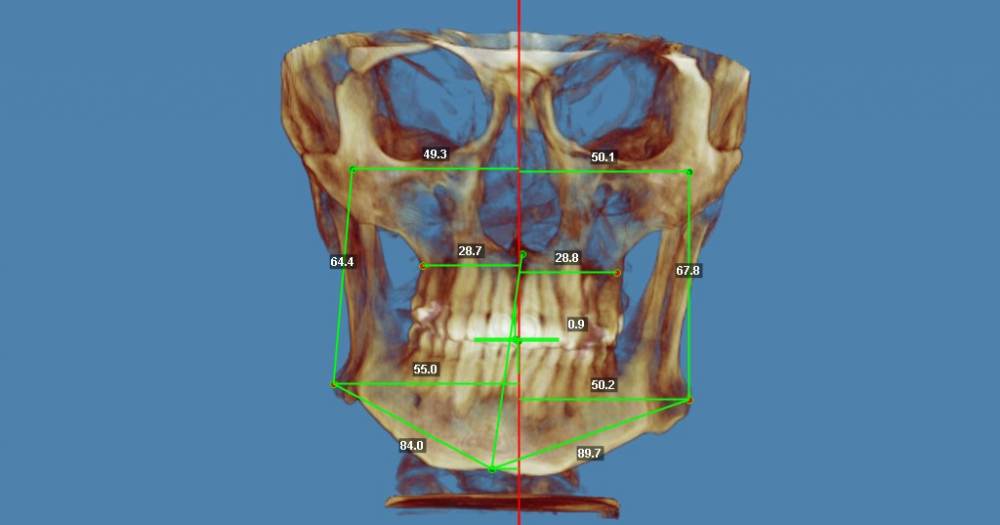

В общем нашел  врача-ортодонт, сделал снимок ортодонт-3 в одном центре и вот сегодня со снимками посетил врача.  Врач сказал, что только в комбинации с челюстной лицевой операцией можно, что то исправить. Подскажите, есть смысл идти к другому специалисту на консультацию что бы все таки без операции? ( Операцию делать не хочу)

фронтальный расчет.jpg